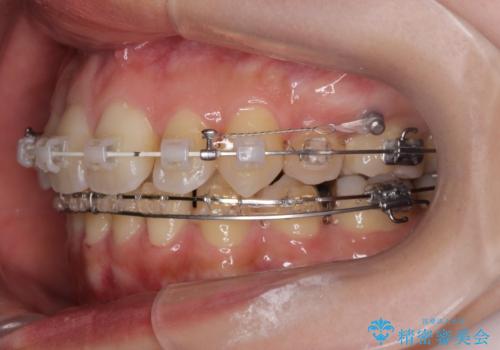

八重歯を矯正治療で治したい!

- 八重歯・がたつきのある歯並びの改善を求めて来院されました。

全部の歯が入り切るスペースがなかったため、小臼歯4本を抜去しワイヤーを用いたマルチブラケット矯正を選択しました。

歯並びの改善と共に、歯ブラシがしやすくなった!と喜んでいただくことができました。